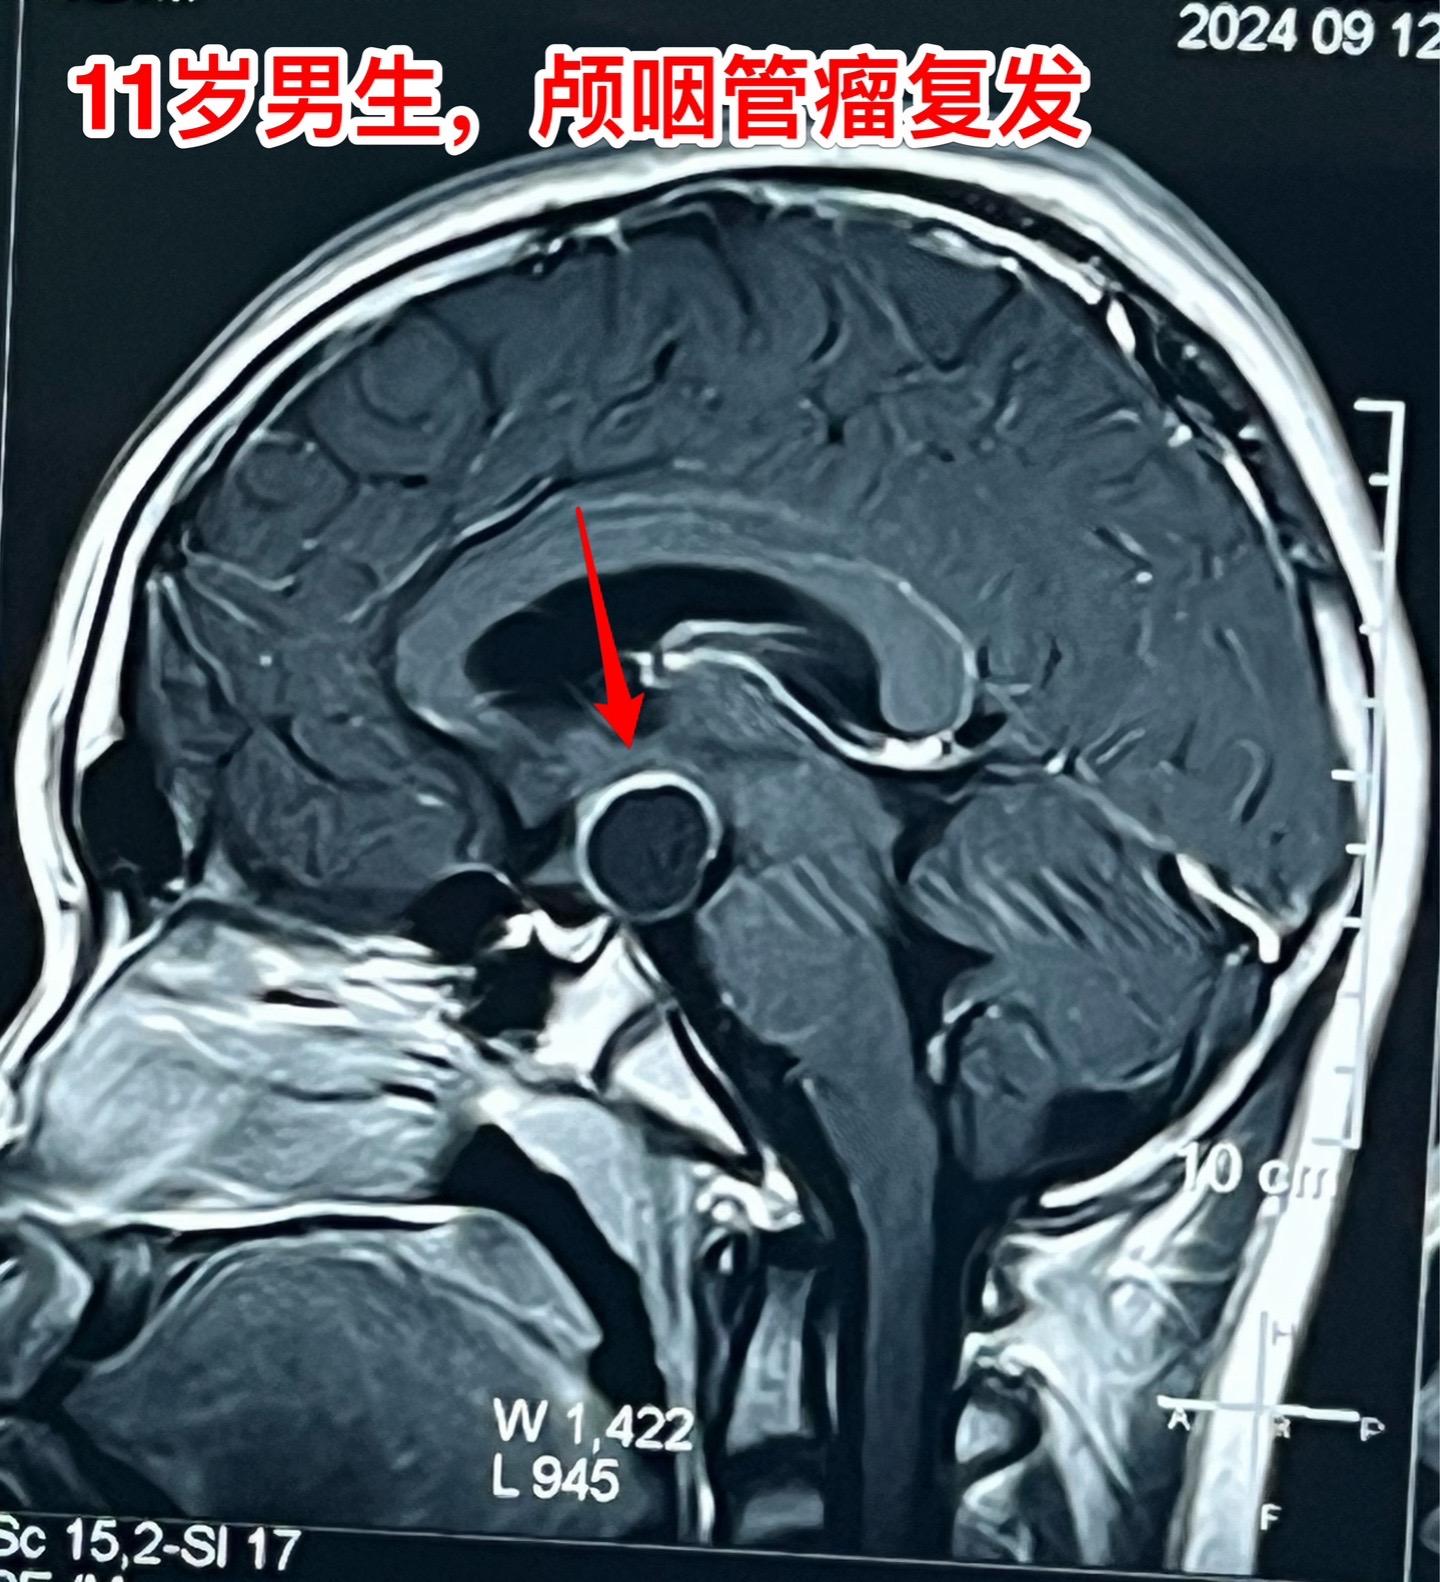

国庆节长假后第一天完成两个手术。一个手是33岁女性,来自云南省香格里拉。因左眼视力下降,到医院检查发现鞍区肿瘤,怀疑是颅咽管瘤。病人没有内分泌功能障碍。影像学上肿瘤是实性的,没有钙化,而且可以看见垂体信号。到底是什么肿瘤呢?今天手术中取肿瘤标本作快速冰冻病理检查,报告是垂体瘤。肿瘤得到完全切除,手术后病人视力好转了。 另一个手术是11岁男孩子,颅咽管瘤复发。经原切口翼点入路将肿瘤完全切除。术前磁共振只看见一个圆形肿瘤,术中发现除了这个肿瘤外还有5个散在的钙化斑,均得到完全切除。这样的散在钙化斑是潜在的危险因